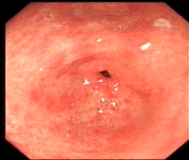

内镜下表现:黏膜红白相间,以白色为主,黏膜皱襞变平或消失,部分黏膜血管显露,可伴有黏膜颗粒或结节状等表现。如伴有肠化生于电子染色窄带成像放大内镜(NBI ME)下发现胃粘膜上皮细胞表面的脑回样结构嵴部的纤细浅蓝色线样结构。病理活检可进一步确诊。

萎缩胃表现